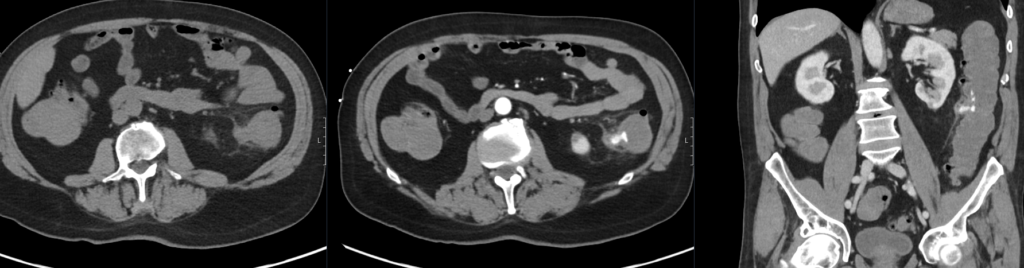

The patient is sent for an urgent CT mesenteric angiogram.

There is arterial blush and portal venous pooling involving an inflamed diverticulum in the descending colon.

Heterogeneous relatively high density fluid throughout the colon and rectum, likely blood products. There is pericolic fat stranding and free fluid.

No extraluminal gas or peripherally enhancing collection.

Extensive background colonic diverticulosis.

This CT demonstrates an acute colonic diverticular bleed.